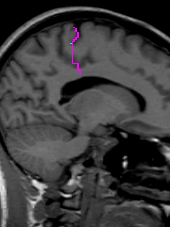

Trace the Central Sulcus in the sagittal view. Select a medial sagittal slice where the “dots” from the sulci lines drawn in the axial view are visible. Trace this sulcus inferiorly to the corpus collosum (Fig 7-8).

Figure 7                  Figure

8